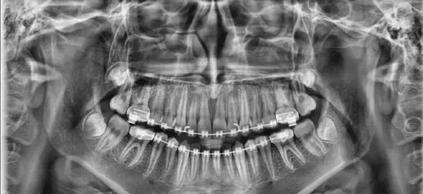

PaX-i 雙傳感器設(shè)備

MSQJ2000-I口腔全景X射線機

產(chǎn)品簡介:

使用了50kHz高頻直流發(fā)生器,進(jìn)口齒科專用X射線管、手動式升降、電磁鎖定等,使其拍片時焦點小,圖像清晰,同時使X射線的輸出更加穩(wěn)定和準(zhǔn)確,從而減少了散射線對病人和操作人員不必要的輻射。并引進(jìn)日本先進(jìn)的scara投照平臺技術(shù)與工藝,使全景投照模式得以極大的拓展。豐富的投照程序選擇,為臨床診斷提供多種、實用的頜面影像信息。先進(jìn)的頜骨體層(全景)掃描技術(shù)方案使掃描聚焦與頜骨達(dá)到最佳彌合。直接成像影像還源性、清晰度均達(dá)到極高水平。

★  除了口腔全景影像,還能拍攝頭顱正、側(cè)位影像、四均分的顎關(guān)節(jié)共四種影像。

拍攝顎關(guān)節(jié)時,只要在取出牙托架和咬合桿后,本機功能即自動切換,即可對左右顎關(guān)節(jié)(開口、閉口)拍攝,具有均衡的放大率,可獲得一張四均分的顎關(guān)節(jié)X射線影像。